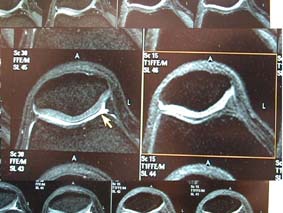

39: ProSet Water exitation。1-2-1を通常使用するが、1-3-3-1を userが選択することもできる。 ProSetでは、骨を低信号に、軟骨を中等度信号に、/0関節液を高信号に描出できる。右はSPIRで、関節液を高信号に 描出できず、1種類の画像に見えるものが少ない。 |